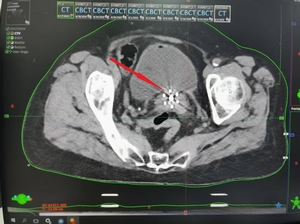

▲插植完成后行CT扫描,显示插植针位置与肿瘤完全吻合

▲计划优化完成后的剂量分布图(100%的剂量包围了整个肿瘤,对正常组织进行了有效保护,大大减少了正常组织的副反应)